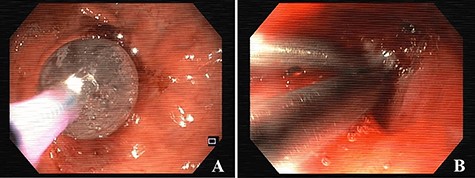

Esophagogastroduodenoscopy images showing dilation of the gastro-jejunal anastomosis (A) and closure of gastro-gastric fistula with clips (B).